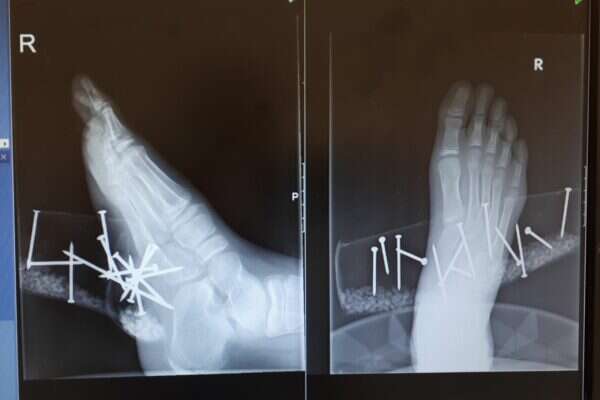

הילד מועבר כעת לחדר הניתוח, כאשר הוא בהרדמה מלאה, על מנת לחלץ את המסמרים שננעצו עמוק בכף רגלו הימנית.

המסמרים חדרו עמוק את כף רגלו הימנית // צילום: מרכז הרפואי זיו